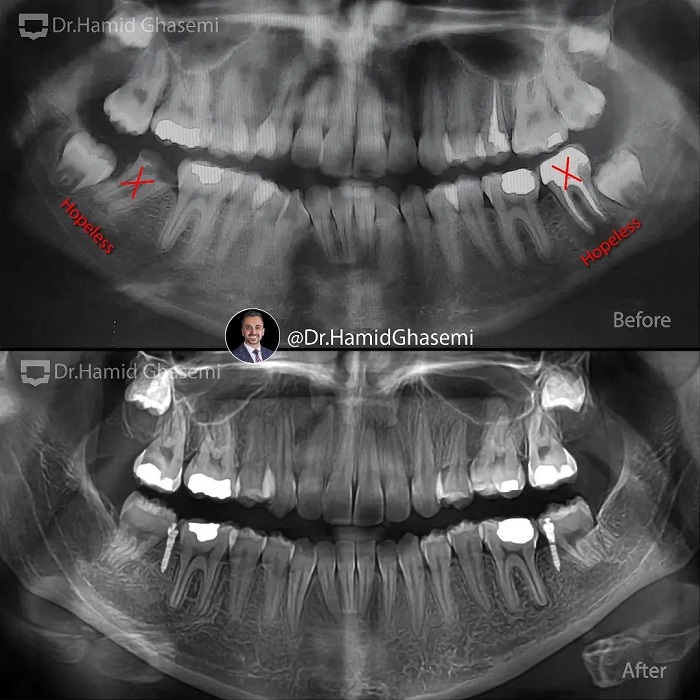

شماره پرونده : M.98_1542

این کیس یک نمونه خوب از استفاده دو تکنیک متفاوت جهت دیستالیزیشن(عقب بردن) در فک بالا و پایین هست. مشکلات کیس عبارتند از: پروتروژن دندانی هر دوفک، کراودینگ شدید دندانی، اپن بایت قدامی در دختر ۱۶ ساله. در فک بالا دیستالیزیشن با کشیدن دندانهای پرمولر دوم (استفاده از تکنیک اسلایدینگ و لوپ مکانیک) انجام شد ولی در فک پایین توتال آرچ دیستالیزیشن(با استفاده از اسکروهای باکال شلف مندیبل) انجام شد به این دلیل که دندانهای آسیاب دوم غیر قابل نگهداری با پروگنوز بسیار ضعیف بودند و در روند درمان دندانهای عقل فک پایین جایگزین دندانهای آسیاب دوم شدند.

This case is a very good example of 2 different biomechanics in upper and lower arch in order to perform distalization. A case is a typical bimaxillary dentoalveolar protrusion with severe crowding and anterior openbite in 16 years old girl. In upper arch i decided to extract upper 2nd premolars in order to perform distalization (using conventional sliding and closing loop mechanics) but in lower arch the best choice was to perform total arch distalization(using buccal shelf screws) since lower 2nd molars were hopeless with very poor prognosis and then lower 3rd molars were substituted accordingly.